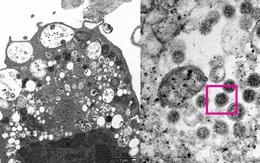

Các nhà khoa học Israel cho rằng đã đến lúc xem xét lại quan điểm Covid-19 là bệnh về đường hô hấp vì nghiên cứu mới cho thấy căn bệnh này thực ra tấn công vào hệ miễn dịch và hô hấp.